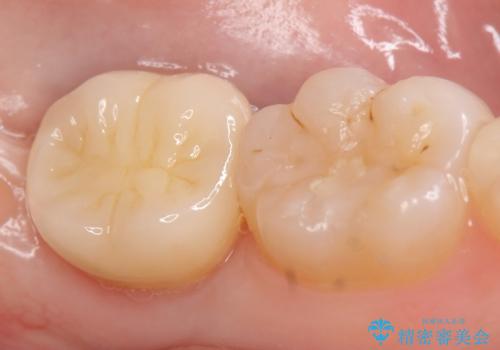

その後歯茎の治りを待ちポケットが正常値であることを確認後、オールセラミッククラウンによる補綴を行いました。

今回用いたオールセラミッククラウンはジルコニアフレームという白い素材の上にセラミックを盛っているため、審美性が非常に高いのが特徴です。

また、ジルコニアは人工ダイヤモンドの材料にも使われているほど高い強度を持っており、そのためオールセラミッククラウンは審美性だけでなく、奥歯やブリッジの補綴も可能とするクラウンです。